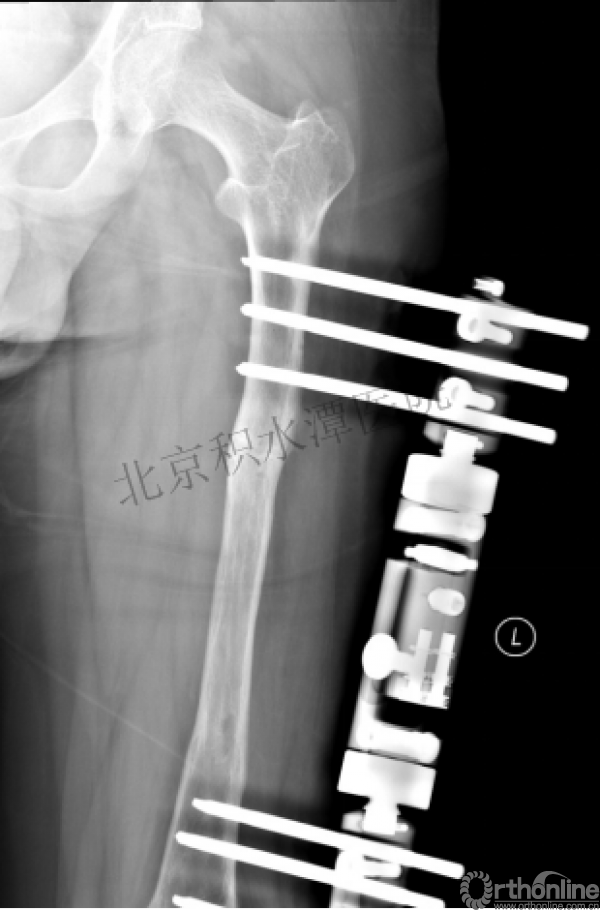

病例分享一

男孩 、5岁,初次骨折于2007年7月。

术后2年→再骨折→再次手术

钢板固定后一年

取板后再骨折→TEN

TEN取出后2个月

闭合复位再固定加尾帽

又过了4年!时间来到2015年

一年以后顺利愈合,实则危机四伏

数月后再骨折!牵引!

髋人字支具

外固定架术后一年

整整11年!是否治疗终结?

病人的付出?医生当反思!